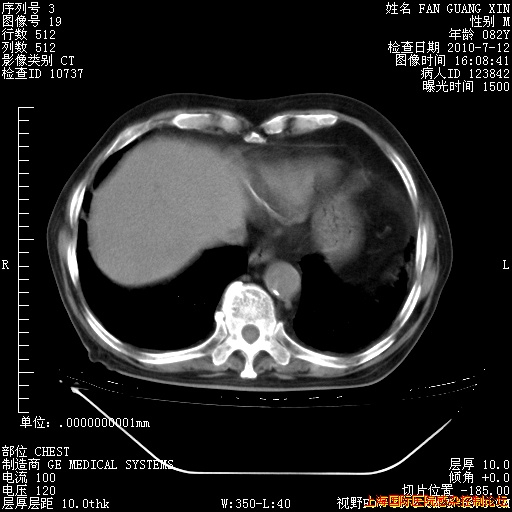

今天复查CT

整整相隔30天的肺部CT好像有所好转啊。甲强龙减量第3天,需要观察体温。

海管,自昨日你和我通完话后,不知您岳父消化道症状有无缓解?体温怎样?阅读7.12日胸部ct,个人认为目前激素治疗是有效的,甲强龙减量是适宜的。因在抗痨治疗,需密切观察肝功、肾功能和血常规。不过,老年、长期住院和大量使用激素,很担心菌群失调发生